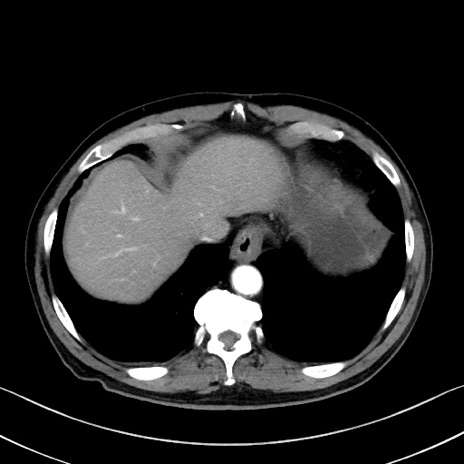

症例35(横断像)

【症例】70歳代 男性

【主訴】腹部膨満、嘔吐

【現病歴】昨日より腹部膨満感出現。本日増悪し、仙痛出現。嘔吐あり、受診。

【既往歴】糖尿病、胆摘後

【身体所見】BP 149/80mmHg、HR 74/min、BT 35.9℃、腹部:膨満、軟、圧痛なし。腸雑音減弱あり。上腹部正中切開瘢痕あり。

【データ】WBC 13500、CRP 1.72